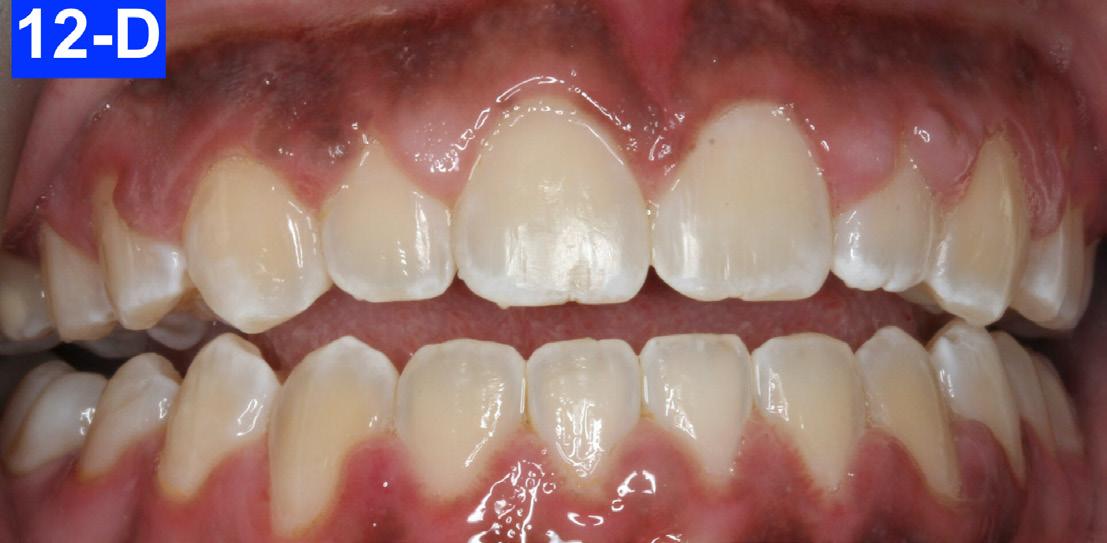

Figures 12-A to 12-M show the post-treatment images at the time of insertion of the retainers. We had an opportunity to evaluate the patient’s occlusion three years post-treatment. Compared to the initial post treatment evaluation, it was noted that the occlusion had settled into an even more stable position after three years.

Fig. 12-H: Post-treatment, MN occlusal view

Fig. 12-J: Post-treatment, posed smile